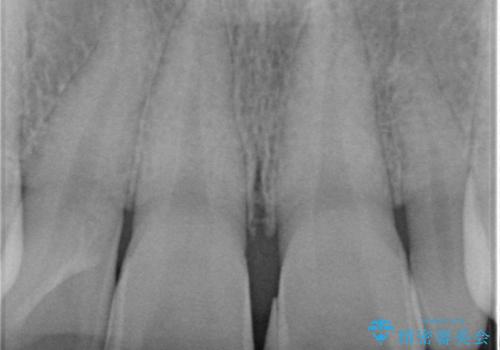

- 隙間を埋めた材料の変色や形を気にして来院された患者様です。

矯正治療などを含めて治療方法を相談した結果、当該歯をオールセラミッククラウンにて補綴治療を行うこととしました。

前歯の単独歯の補綴治療であったので、オーダーメイドタイプをおすすめしましたが、今回は既製タイプにて製作を進めました。

既製タイプでしたが、違和感のない仕上がりとなりました。